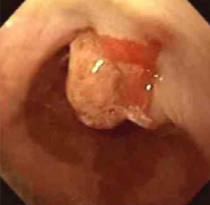

我让患者在门诊做了一个上消化道造影,基本上确诊了。入院后完善检查,明确是食管癌,可惜病变位置太高,如果手术的话需要全食管全喉切除,这对一个41岁的人来说太残忍了,更要命的是发现颈部淋巴结多发转移了,不考虑外科治疗了,这个病人的预后可想而知。